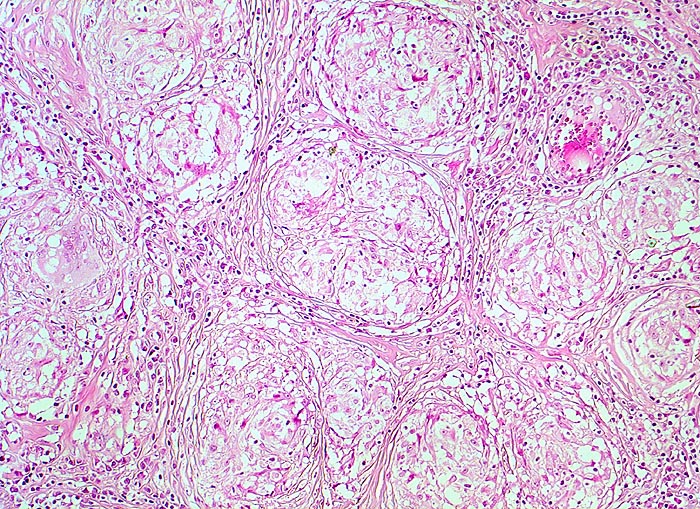

PathoPic – image database / PathoPic ID 4015 - Lymphknotensarkoidose (Morbus Boeck) Granulome mit Fibrose

Lymphknotensarkoidose (Morbus Boeck) Granulome mit Fibrose

Lymphknoten, inguinal

Späteres Stadium einer Sarkoidose. Für Sarkoidose typische konzentrische Fibrose in der Peripherie der Granulome. Das Parenchym des Lymphknotens ist verdrängt. Die Granulome stehen Rücken an Rücken und konfluieren nicht.

Bihiläre Lymphadenopathie bei Sarkoidose. Plötzlicher Herztod.

Histologie

100

42

männlich